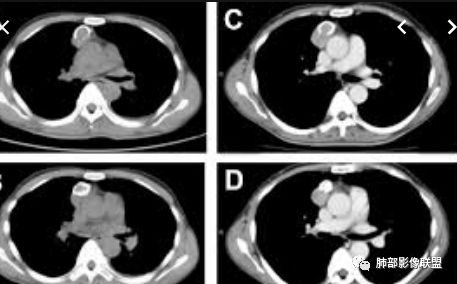

实性部分密度与肌肉类似,钙化粗大、结节状

右侧内乳动脉增粗

实性部分中度强化——增加20~27HU

深分叶,边界尚清,附近未见肿大淋巴结

弹指之间:定位:1.非肺内来源,2.纵隔或胸膜来源;内乳动脉增粗,cor示与胸膜关系密切;

定性:特点是粗大钙化,延迟强化;首先排除畸胎瘤(无脂肪、有延迟强化);胸腺肿瘤的粗大钙化罕见;综合:SFT>胸腺瘤(高危)。